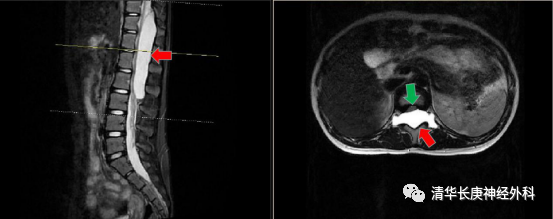

“神泌-双镜”首亮相 微创治愈11岁少女巨大椎管内囊肿